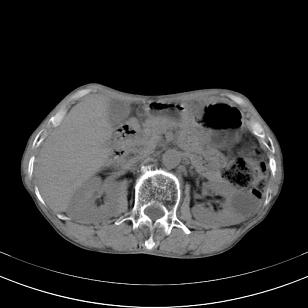

标题: 男,65岁,反复右上腹痛, [打印本页]

标题: 男,65岁,反复右上腹痛,

胃镜提示十二指肠占位